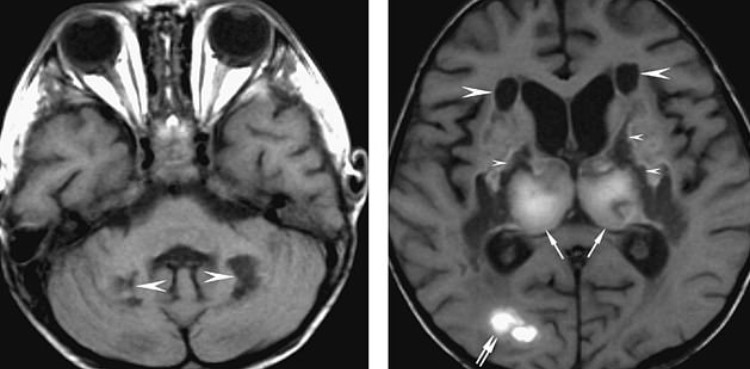

Neurological symptoms are not considered typical of coronavirus, so the doctors also performed a CT scan of her brain.

Dark spots on the resulting can indicate that parts of her brain are less dense than they should appear in a healthy brain.

That told the woman’s doctors that either fluid had built up in these regions, or chunks of her brain cells had died off.

In particular, the woman’s thalamus showed damage. The thalamus sends sensory information from the far reaches of the body to the cerebral cortex, which processes those signals.

Further scans revealed the woman’s brain also had lesions, or brain bleeds, in her temporal lobes, which are involved consciousness and memory as well as sensation.

Taken together, the scans confirmed the doctors’ suspicions.

The team had suspected encephalitis at the outset, but then back-to-back CCT and MRI scans made the diagnosis.

Encephalitis is a dangerous brain swelling condition that can come on as a result of any number of kinds of trauma, as well as severe infections.